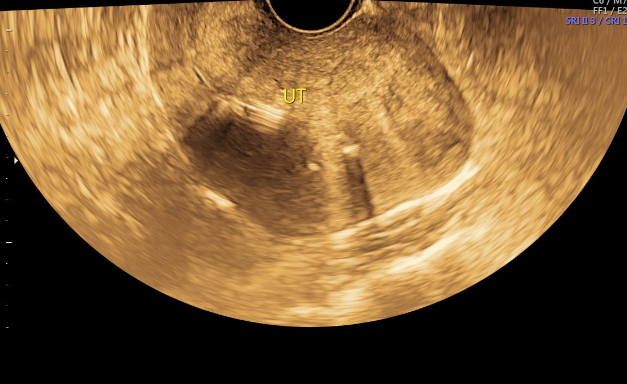

患者未诉术后点滴出血淋漓不尽、下腹痛等不适,2024-10-07月经来潮,6天干净,2024-10-15经阴道妇科彩超提示:子宫呈后位,子宫切面内径72mm*54mm*65mm,形态失常,体积增大,宫内肌层回声不均,见细小的增强回声区和低回声区交织混杂,内膜线前移,内膜厚4mm,光整,节育器距宫底19mm。双附件区未见占位病变,子宫直肠窝内未见液性暗区,CDFI未见明显血流信号。现术后1年余,月经规则,2-3/28-30天,量少,无痛经。